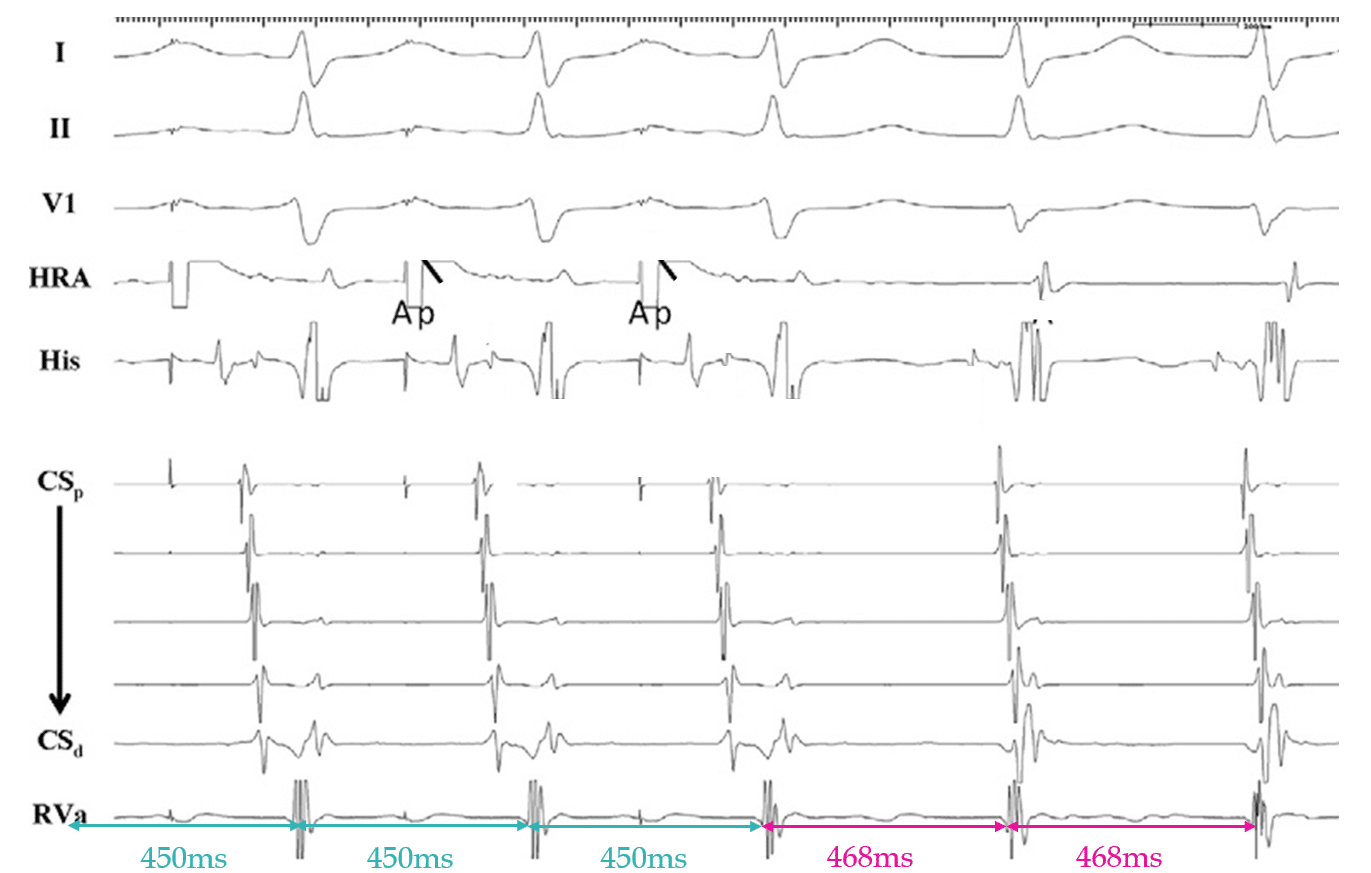

This EGM was obtained from a 46 year old female with presumed AVJRT. After many ablations in the slow pathway region, tachycardia could still be induced, arousing suspicion that perhaps this SVT was not typical AVJRT. Following this, atrial overdrive pacing was performed during tachycardia. What does the below result indicate?

(figure based on: Fan R et al. Novel use of atrial overdrive pacing to differentiate junctional tachycardia from AVNRT. Heart Rhythm. 2011;8(6):840–4)

Answer: This EGM is diagnostic of a focal arrhythmia arising from the His Bundle/AV node due to an AHHA response following successful atrial overdrive pacing, consistent with Junctional Ectopic Tachycardia.

Pacing the atrium 20ms faster the the TCL is useful in differentiating JET from AVJRT in patients with 1:1 AV conduction.

You must accelerate tachycardia to your pacing cycle length and the tachycardia must continue at it’s original TCL.

1. An AHHA response is diagnostic for JET.

2. An AHAH response indicates Reentry (AVJRT/AVRT).

Top tip: Always confirm your last entrained His/V signal! Measure it, don’t assume it.